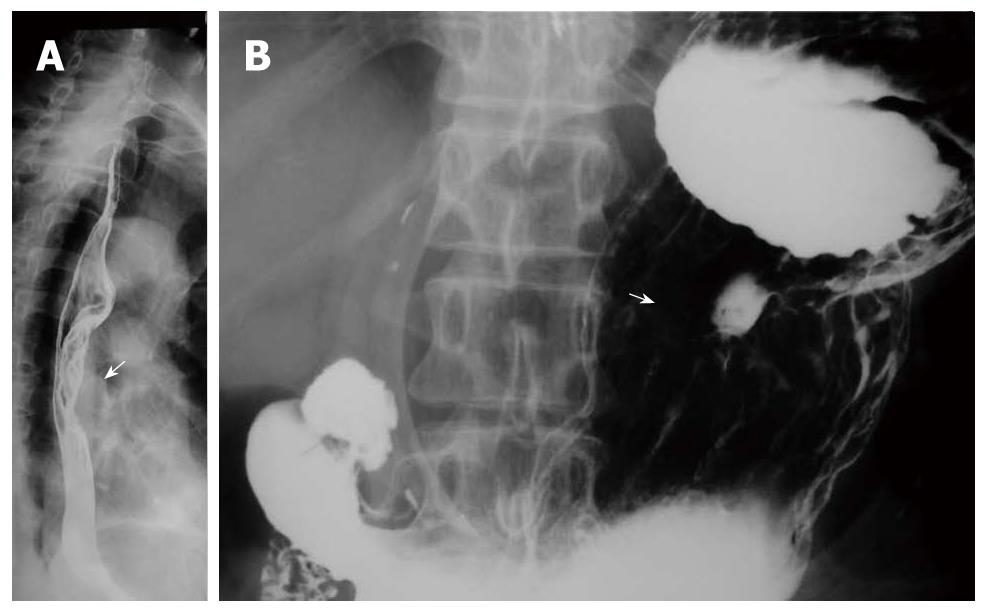

Gastric cardia radiology. Diagnostic centers of america dca is a leading diagnostic imaging facility offering a full array of imaging services in palm beach county florida. We have five state of the art radiology imaging centers in boca raton boynton beach delray beach and wellington florida. The gastric cardia is characterized on barium stud ies by three or four stellate folds that radiate to a central point at the gastro esophageal junction also known as the cardiac rosette fig 2 12. Variations and benign influences may closely resemble the more dangerous lesion.

Thick tortuous folds or lobulated filling defects in the cardia or fundus. Right gastroepiploic artery inferiorly and left gastroepiploic artery and short gastric arteries superiorly fundus of the stomach. Results of surgical treatment of carcinoma of the esophagus and gastric cardia. The collection of cases presented here comprises only that material which is rare in our experience or quite new to us.